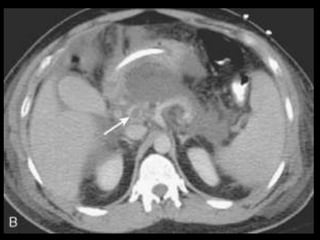

Coleções líquidas agudas

Ocorrem em cerca de 40% dos casos;

Podem ser em torno da glândula ou extra-

pancreático;

Carecem de cápsula e são confinadas ao espaço

anatômico onde se encontram;

Podem dissecar para outros locais: mediastino,

pararrenal posterior, órgãos sólidos ou parede de

alça intestinal.

Coleções líquidas agudas- TC

Hipodensas

Mal definidas

Sem cápsula ou parede reconhecível

Resolução espontânea em 50% dos casos;

Complicações: dor, infecção secundária e

hemorragia;

São passíveis de drenagem percutânea caso não

regridam ou se tornem infectadas.